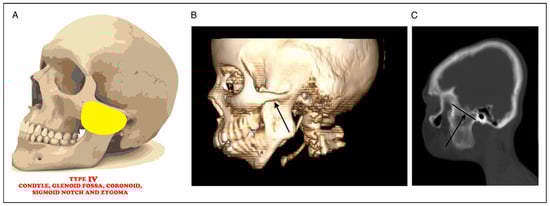

Regarding the new classification system of MMS in noma patients, 6 (9.4%) patients presented with Type 1 (Mild joint obliteration)±Soft tissue scarring (Figure 1A–C), 24 (37.5%) presented with Type II (Total joint obliteration) ±Soft tissue scarring (Figure 2A–E), 21 (32.8%) presented with Type III (Coronoid, zygoma and maxilla)±Soft tissue scarring (Figure 3A–E), 4 (6.3%%) presented with Type IV (Condyle, glenoid fossa, coronoid, sigmoid notch, and zygoma)±Soft tissue scarring (Figure 4A–C), 7 (10.9%) presented with Type V (Condyle, glenoid fossa, coronoid, sigmoid notch, zygoma and pterygo-maxilla)±Soft tissue scarring (Figure 5A–D), while 2 (3.1%) patients presented with Type VI (condyle, glenoid fossa, coronoid, sigmoid notch, zygoma, pterygo-maxilla and the orbit) ±Soft tissue scarring (Figure 6A–D) (Table 2).

Figure 4.

(A) Picture showing bony fusion between condyle, glenoid fossa, coronoid, sigmoid notch, and zygoma. (B): 3D CT radiograph showing fusion between condyle, glenoid fossa, coronoid, sigmoid notch, and zygoma (black arrow). (C) Sagittal CT radiograph showing fusion between condyle, glenoid fossa, coronoid, sigmoid notch, and zygoma (black arrow).

Type IV MSS (Condyle, glenoid fossa, coronoid, sigmoid notch, and zygoma)±Soft tissue scarring.